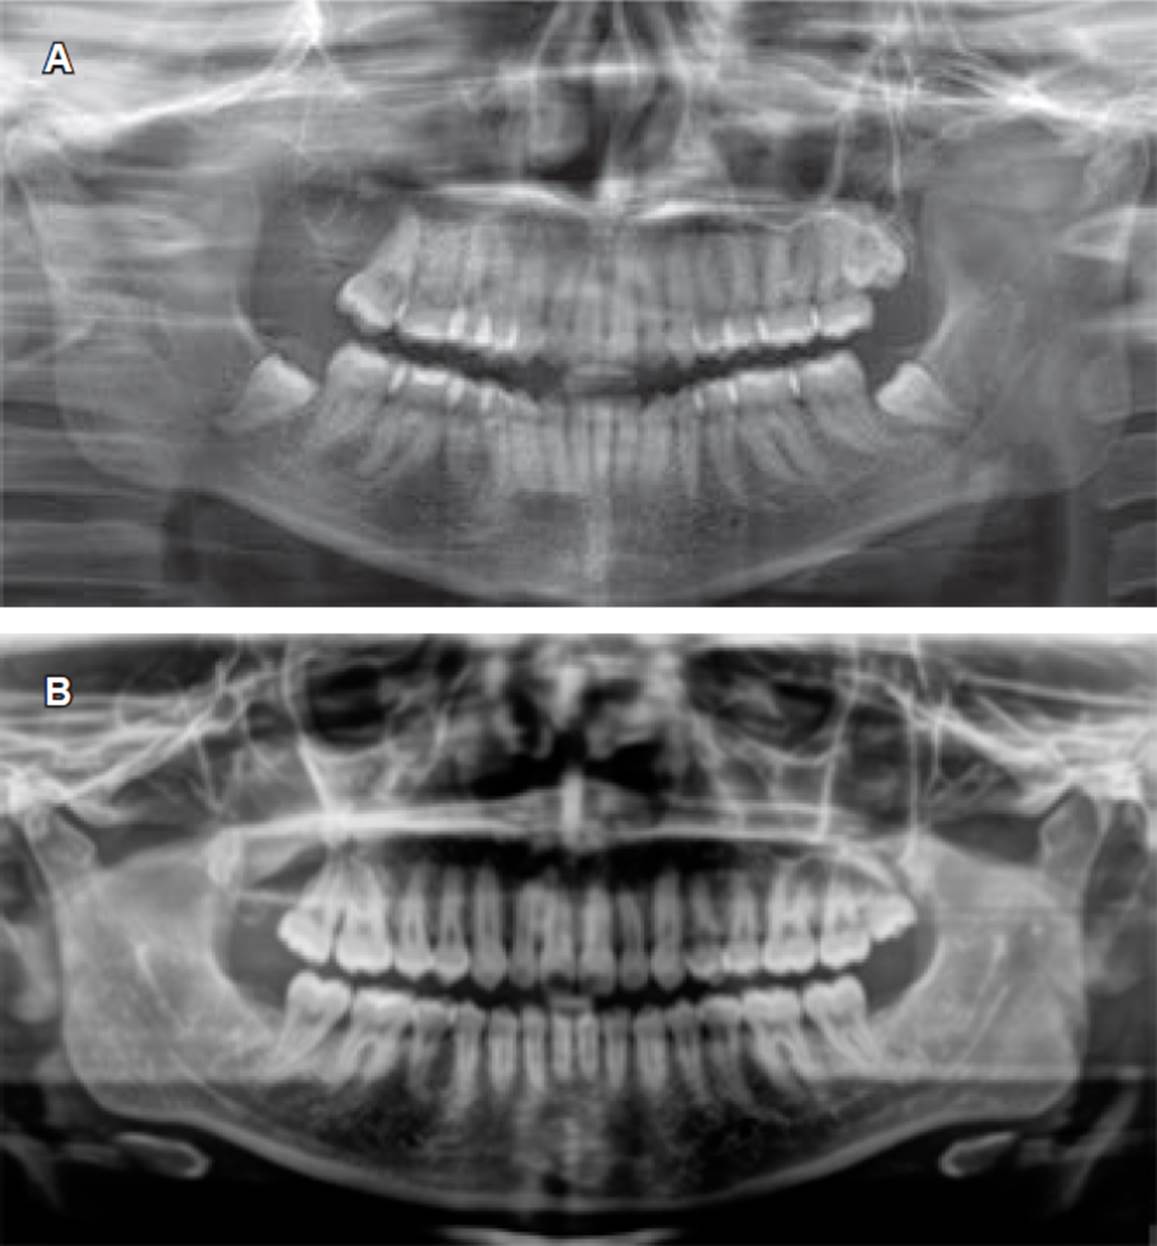

Figura 3 Ortopantomografía. A) Ocho meses posteriores a la descompresión quística, se observa la ausencia de OD 18 y cavidad quística delimitada con bordes definidos. B) Control a treinta meses posteriores a enucleación y aplicación de 5-fluorouracilo.

En la actualidad, la paciente sigue en control radio gráfico y no se ha reportado ningún indicio de recidiva posterior a tres años, se observa el sitio de la lesión con adecuada evolución y formación de hueso en la cavi dad quística (Figura 3B). Se requiere un seguimiento a largo plazo para confirmar el éxito del tratamiento, por lo cual se indicaron citas de control por al menos cinco años y control radiográfico cada tres a cuatro meses.